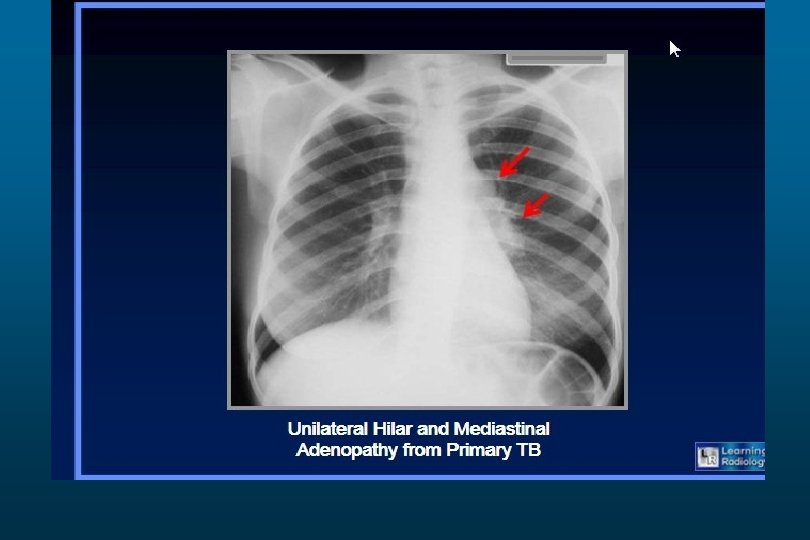

Tuberculosis